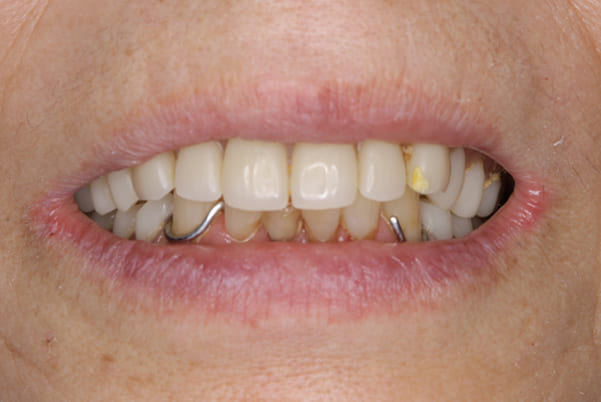

治療用入れ歯

治療用入れ歯は患者様とご相談し、早急にお痛みをとり、お食事ができることをご希望されていたため、歯を抜くと同時に仮の入れ歯が入りお食事をされた後のお写真です。直ちに、お痛みを取り除き、お食事ができるような治療計画としました。